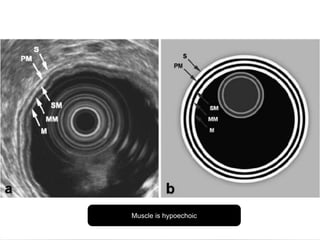

Endoluminal Ultrasonography

Using flexible endoscope with a 7.5 to

12 megahertz transducer

Stomach is filled with water to provide

acoustic window

Can detect perigastric and celiac lymph

nodes 5 mm or greater in size

Disadvantages: operator dependant,

lymph nodes smaller than 5 mm with

metastasis not detected

Muscle is hypoechoic